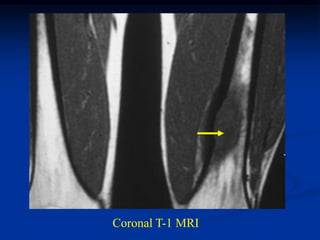

Coronal T-1 MRI